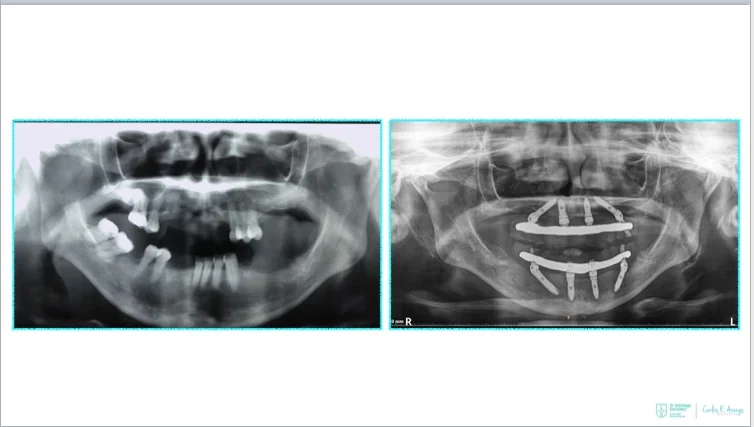

What is the All-on-4 treatment concept?

The All-on-4® treatment concept is a cost-efficient, graftless solution that provides patients with a fixed full-arch prosthesis on the day of surgery.

- Full-arch rehabilitation with only four implants

Two straight anterior implants and two implants tilted up to 45º in the posterior - Immediate Function (fixed provisional bridge)

For patients meeting criteria for immediate loading of implants - Graftless Procedure: Bone grafting is avoided by tilting the posterior implants, utilizing available bone.

Smile Again: Full mouth dental implants

Four implants can replace all of the teeth on the top or the bottom! Dental implant technology advances have paved the way for innovative new solutions.

surgery quickly leads to improved patient satisfaction – with regards to function,

aesthetics, sense, speech and self-esteem.

need for time-consuming bone grafting procedures, while immediate loading

shortens time-to-teeth.